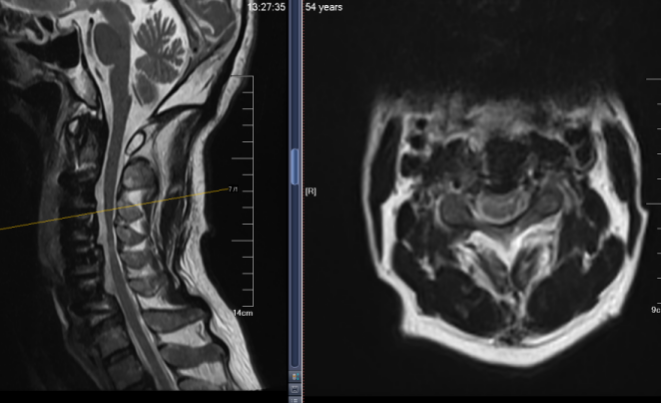

术后复查的核磁共振影像清晰地显示,那块压迫脊髓的“巨石”已被整体前移,受压的脊髓成功“解套”,重新恢复了舒展的形态。

术后影像显示,患者骨化物可控前移、打开椎管空间,脑脊液带恢复、脊髓和神经根得到原位减压